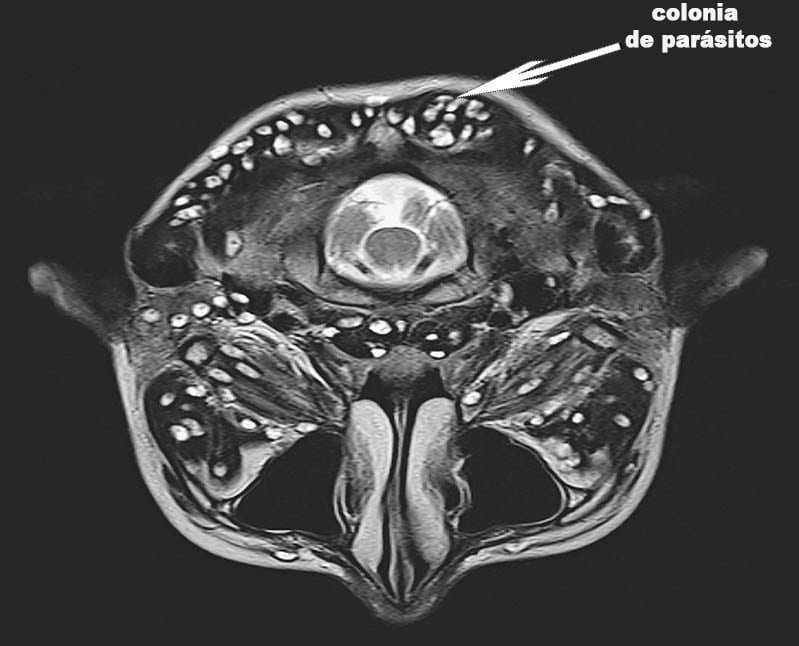

Uno de los tipos de parásitos más comunes:

Los parásitos provocan necrosis tisular, que prácticamente conduce a la amputación:

El parásito se alimenta de nuestros tejidos blandos:

Un pulmón destruido desde el interior por parásitos: